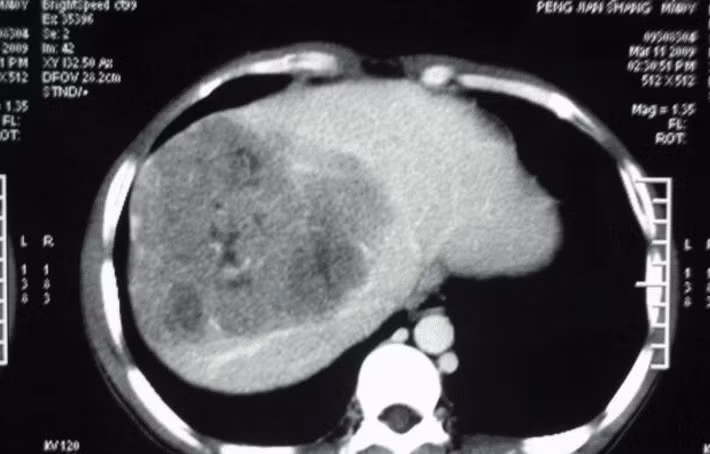

Sau nhiều lần kiểm tra tại bệnh viện, bác sĩ phát hiện ra rằng alpha-fetoprotein trong cơ thể của cô Vương Khiết vượt quá tiêu chuẩn nghiêm trọng, chẩn đoán là ung thư gan giai đoạn giữa, phải nhập viện ngay lập tức.